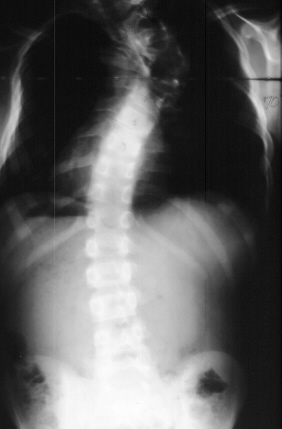

Significant findings are the cafe-au-lait spots on torso and extremities, axillary and inguinal freckling, plexiform neuroma right flank, obvious kyphosis and scoliosis with shortened trunk in relation to extremities, ligamentous laxity of fingers and elbow. Gait, reflexes and neuromuscular exam are all normal.

In preparation for spinal fusion for stabilization of this kyphoscoliosis he underwent a MRI of the brain cervical and thoracic spine and CT of the thorax. The brain and cervical spine showed no evidence of tumor. The lower cervical and upper thoracic canal was enlarged without evidence of cord compression, a finding consistent with dural ectasia . There is soft tissue protrusion into the thoracic canal that may resemble a dumbbell lesion.

Coinciding with current literature recommendations for treatment of severe dysplastic kyphoscoliosis, the patient underwent an Anterior-Posterior spinal fusion from T1-T10. The scoliosis was corrected to 21 degrees and kyphosis to 34 degrees. The procedure was augmented with a rib strut graft and was tolerated well. No neurologic complications occurred and the patient developed a solid fusion by one year without progression of the curvature. He is currently 5 years post-op playing in sports and without pain.